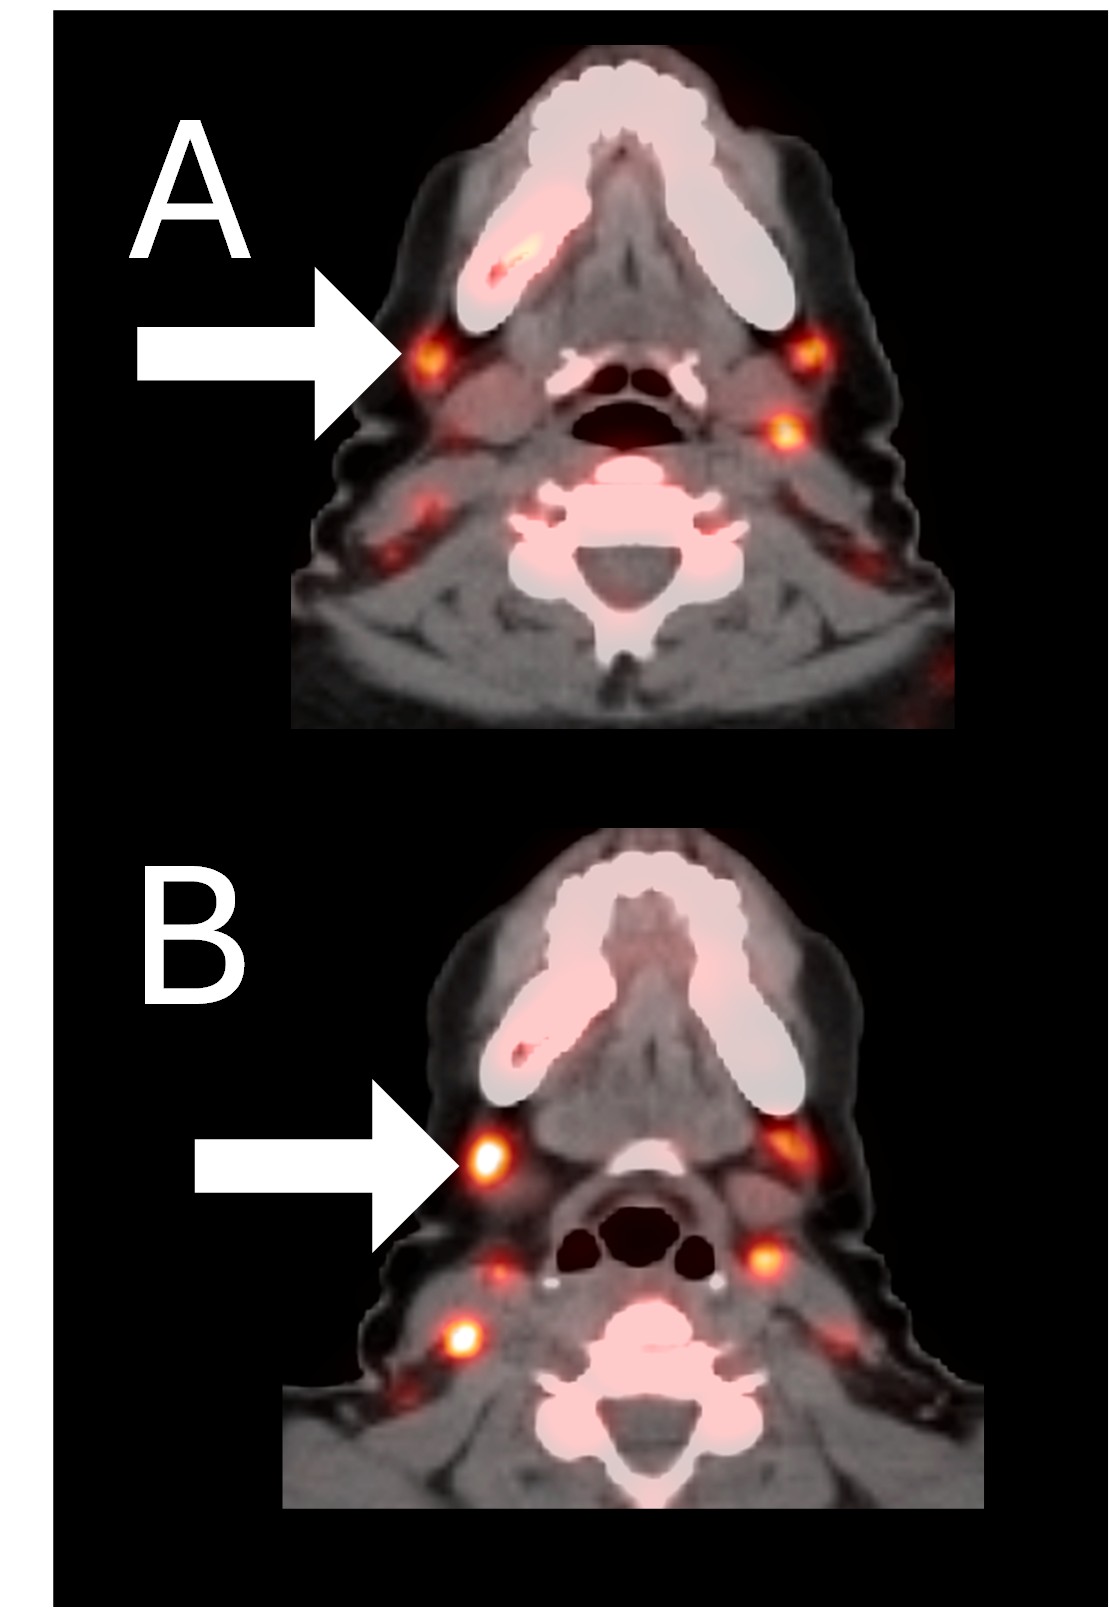

Before BriaCell Treatment Image A: CD8 ImmunoPET image

Pre-treatment imaging of cervical (neck) lymph nodes with moderate uptake indicating presence of some CD8+ cytotoxic (“killer”) T cells.

After BriaCell Treatment Image B: CD8 ImmunoPET image

Post treatment enhancement of cervical (neck) lymph nodes indicating immune system activation and increased presence of CD8+ cytotoxic T cells.

Example 2 Images (Patient 15-005):CD8 ImmunoPET images pre (A) and post (B) Bria-IMT treatment